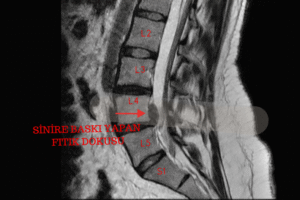

Yaşlanmanın doğal bir sonucu olarak vücudumuzda bazı yapısal değişiklikler meydana gelir. Bu değişikliklerden biri de omurgada görülen daralmadır. Tıbbi adıyla “spinal stenoz” olarak bilinen omurga kanal daralması, sinir köklerinin geçtiği kanalın zamanla daralması sonucu ortaya çıkar. Bu durum, sinirlerin baskı altında kalmasına yol açar ve hastada günlük yaşamı zorlaştıracak seviyede ağrı ve hareket kısıtlılığına neden olabilir.

Omurga kanal darlığı genellikle 40 yaş üzeri bireylerde görülür. Yaşlanmaya bağlı olarak omurgada bulunan disklerin yapısında bozulma, bağ dokularının kalınlaşması ve kemik çıkıntıların oluşması gibi değişiklikler omurilik kanalını daraltabilir.

Bu daralma sonucunda omurilik ve sinir kökleri baskı altında kalır. Bu baskı; bel ağrısı, bacaklarda uyuşma, karıncalanma, kas güçsüzlüğü ve özellikle yürüyüş mesafesinde belirgin azalma gibi belirtilerle kendini gösterir. Bazı hastalar birkaç yüz metre bile yürüyemediğini, sık sık oturup dinlenmek zorunda kaldığını ifade eder.

Bununla birlikte belirtiler tek başına kesin tanı koymak için yeterli değildir. Manyetik Rezonans Görüntüleme (MR), omurga kanalının yapısını, sinirlerin durumunu ve daralmanın seviyesini en net gösteren yöntemdir. MR sayesinde omurilik ve sinir köklerine baskı olup olmadığı milimetrik hassasiyetle değerlendirilir.

Kanal darlığına eşlik edebilen önemli bir diğer durum ise **hareketli bel kayması (spondilolistezis)**dır. Bu kaymanın varlığını ve hareketle artıp artmadığını anlamak için dinamik lomber grafiler (fleksiyon-ekstansiyon grafileri) kullanılır. Bu görüntüleme yöntemi, omurların anormal şekilde öne ya da arkaya kayıp kaymadığını göstererek tedavi planlamasında kritik rol oynar.